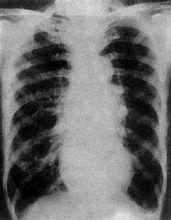

檢查心臟

檢查心臟:

胸片右圖示心臟擴大

心形呈球形